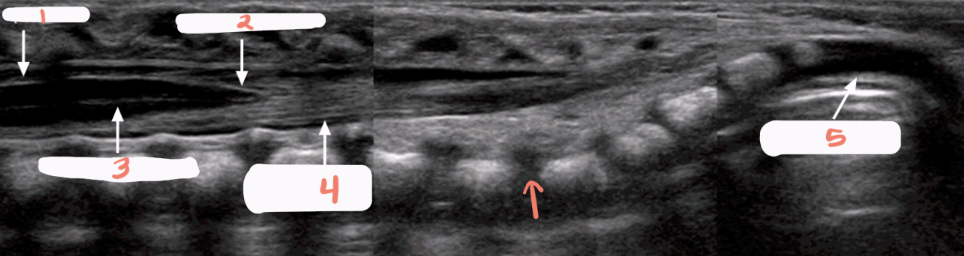

1

subarachnoid space

2

cartilaginous spinous processes

3

dura mater

4

epidural space

5

central echo complex in hypoechoic spinal cord